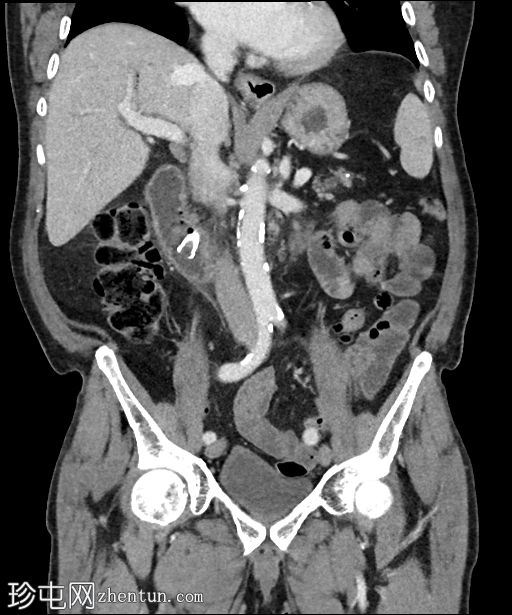

矢状位增强扫描(门静脉期)

3.jpg

可见胆道支架位置良好,管腔内可见分层气液平面。支架远端位于充满液体的D2段内。支架内未见明显放射性结石。

肝内胆管未扩张,但可见胆道积气。

胰头水肿,伴胰周脂肪浸润。未见明显积液。

胰头局灶性结节(代表已知的肿瘤),伴有上游主胰管扩张,位于萎缩的胰颈、胰体和胰尾内。背景可见胰腺实质内钙化。